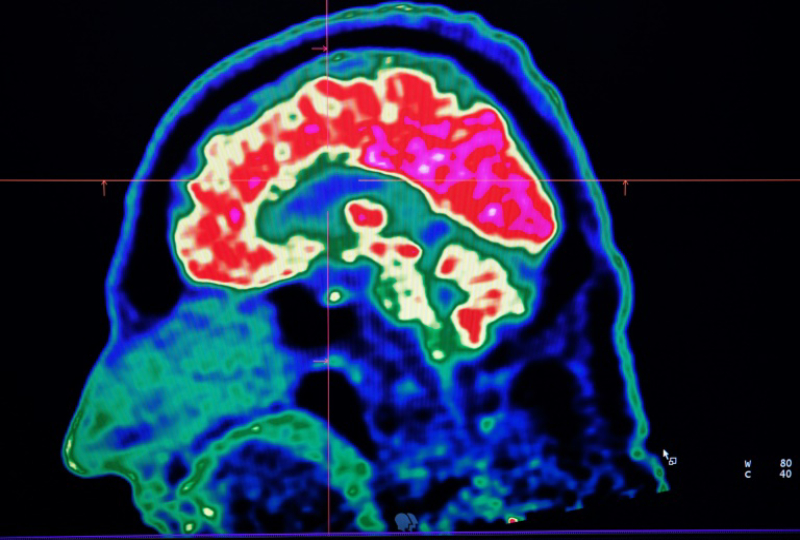

A new study published in Cell Reports on Tuesday honed in on the brain circuitry responsible for upgrading or downgrading these pain signals, likening the mechanism to how a home thermostat controls room temperature.

Yarimar Carrasquillo, the paper's senior author and a scientist for the National Center for Complementary and Integrative Health (NCCIH), told AFP the region responsible was the central amygdala, which according to her work appeared to play a dual role.

Studying mice, Carrasquillo and her colleagues found that the activity in neurons that express protein kinase C-delta amplified pain, while neurons that express somatostatin inhibited the chain of activity in the nerves required to communicate pain.